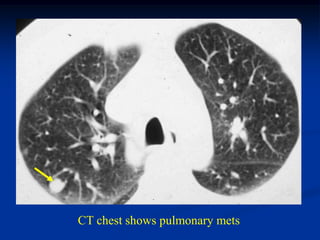

CT chest shows pulmonary mets

CT chest showspulmonary mets